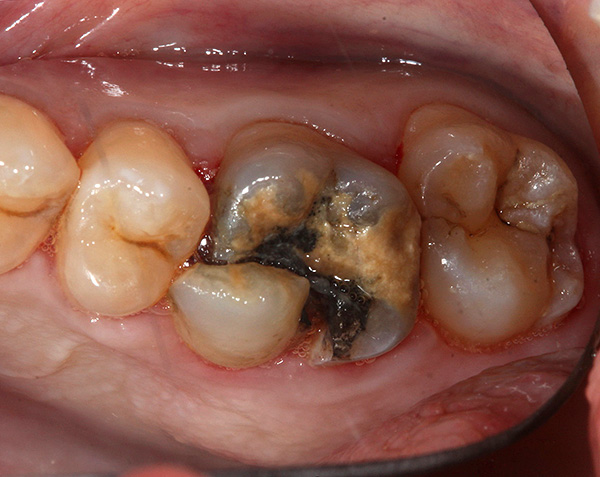

La foto sotto mostra la radice del dente rotto da rimuovere:

Come avviene l'estrazione di denti gravemente danneggiati e quanto costerà?

Molte persone che si trovano di fronte alla necessità di rimuovere un dente gravemente danneggiato sono preoccupate per un momento del genere: un chirurgo dentista sarà in grado di afferrarlo con una pinza, perché in realtà non c'è nulla da afferrare.